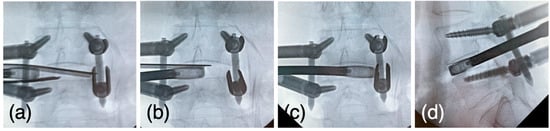

Case 1: A 70-year-old woman was diagnosed with degenerative spondylolisthesis of the L4 vertebra with instability by X-ray, CT, and MRI. VAS for back and leg pain were 100 and 60 mm, and the JOA score was 18/29. The spinal canal area was 95 mm2 at L4/5 disc level, and the % slip was 21% (Figure 7a–d). After the failure of conservative treatment, PETLIF was performed. One month after surgery, VAS back and leg pain improved significantly to 0 and 10 mm. Postoperative X-ray and MRI showed that the % slip was 0%, and the spinal canal area was expanded to 153 mm2 (Figure 7e–h). Bone fusion of L4/5 was confirmed by X-ray and CT scan one year after the surgery (Figure 8a–d).

Figure 7.

(a,b) Preoperative X-ray showing 2° L4 spondylolisthesis. (c,d) Preoperative MRI showed lumbar spinal stenosis at the L4/5 level. (e,f) Postoperative X-ray showed L4 spondylolisthesis was reduced to 0%. (g,h) Postoperative MRI showed the spinal canal area was expanded.